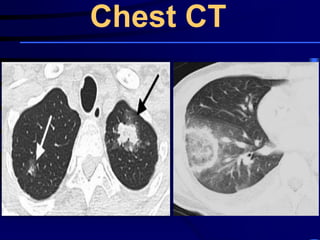

Chest CT

Chest CT can detect pleural effusion, lung abscess, or

It may also detect noninfectious causes such as

bronchiolitis obliterans organizing pneumonia .

Since empyema and parapneumonic effusion can

contribute to nonresponse, thoracentesis should be

performed in all nonresponding patients with

significant pleural fluid accumulation.